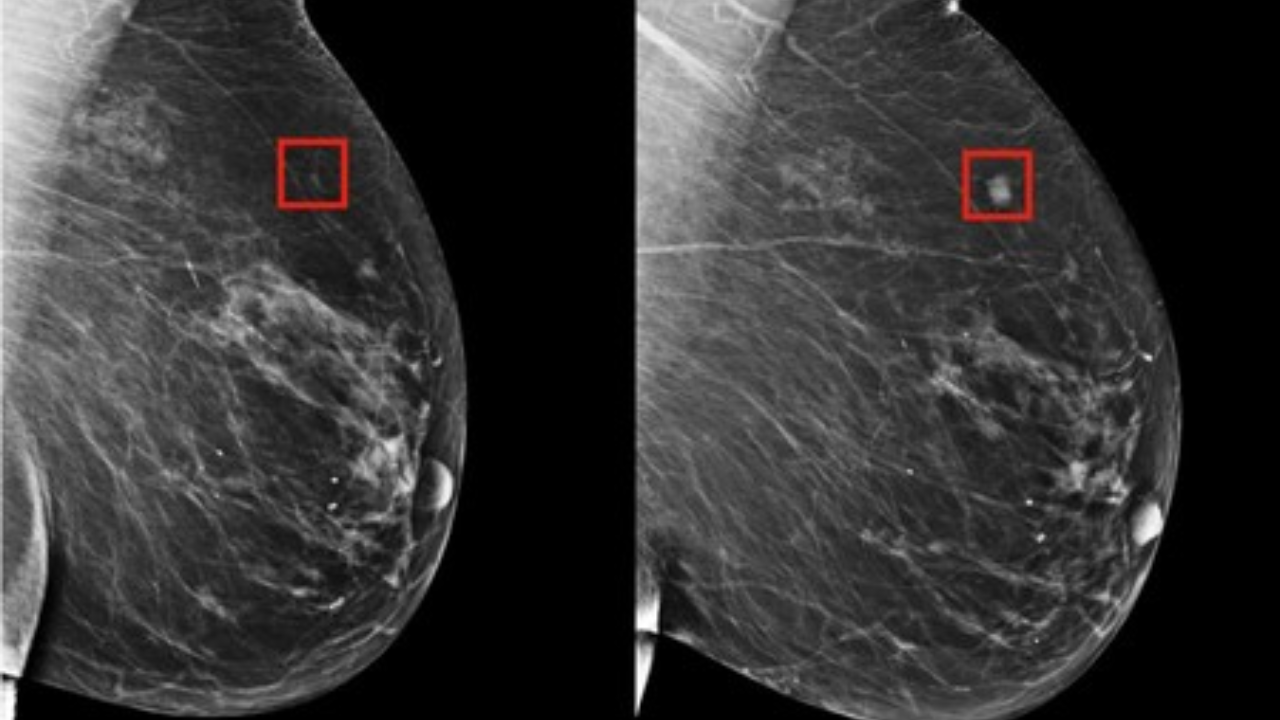

Tecnología

Herramienta de inteligencia artificial puede detectar el cáncer de seno en mujeres